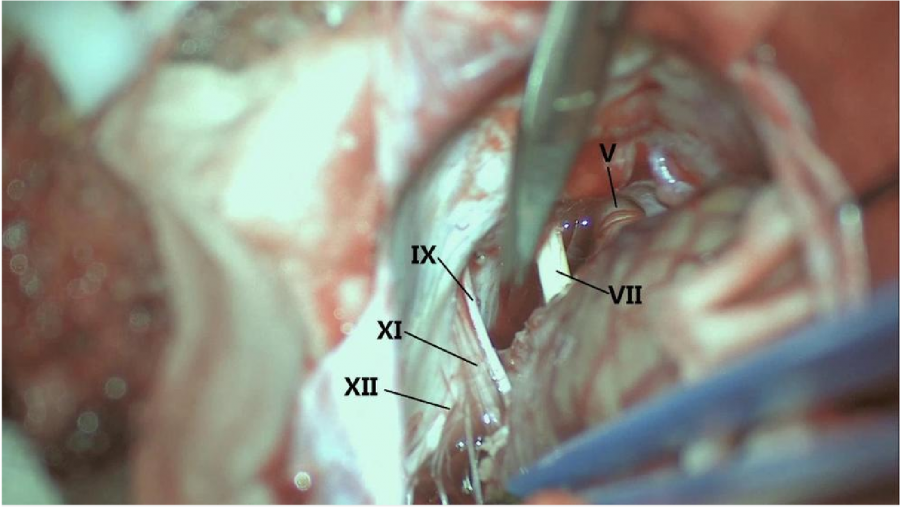

⾏左侧远外侧⼊路脑⼲⾎管畸形切除术,术中所⻅:

3、脑⼲动静脉畸形⼿术切除是注意辨别供⾎动脉与引流静脉,其往往不似其他部位的动静 脉畸形,有叫粗⼤的引流静脉。术中如果不能辨清各⾎管来源与去处,往往会造成不可估量的损失。

4、脑⼲动静脉畸形团周围玩个昂存在复杂的神经及⾎管,操作难度⼤。